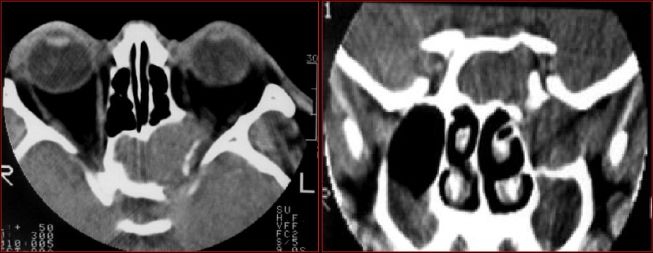

慢性多发鼻窦炎鼻息肉